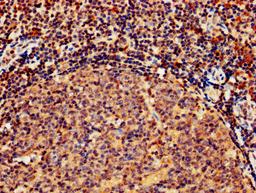

IHC image of CSB-PA010082LA01HU diluted at 1:800 and staining in paraffin-embedded human tonsil tissue performed on a Leica BondTM system. After dewaxing and hydration, antigen retrieval was mediated by high pressure in a citrate buffer (pH 6.0). Section was blocked with 10% normal goat serum 30min at RT. Then primary antibody (1% BSA) was incubated at 4°C overnight. The primary is detected by a biotinylated secondary antibody and visualized using an HRP conjugated SP system.